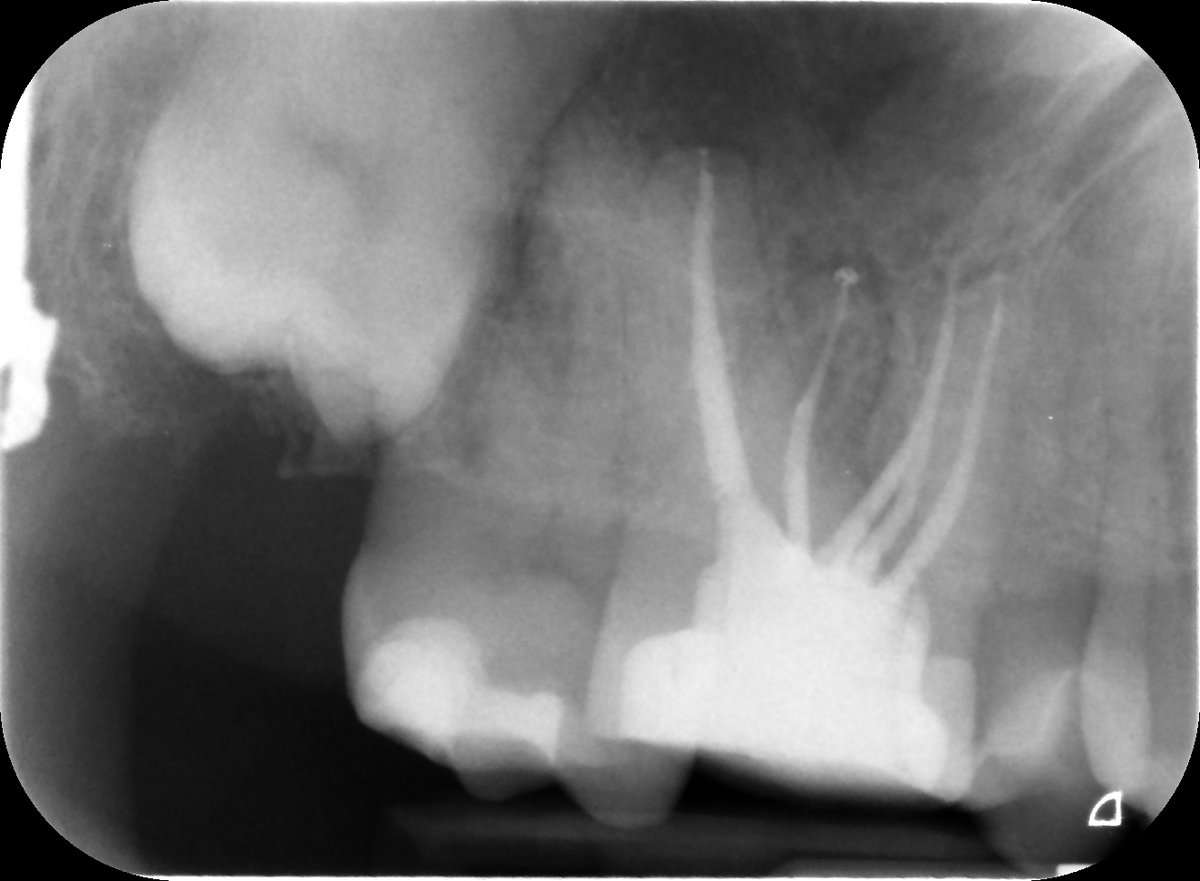

Happy Days in Endoland Saturday Surgery and saving teeth 🤣 UR6 referred for endo after difficulty finding canals. 5 canals in total, EdgeOne Fire preps. Onlay required. Review in 9 months. #savingteeth #endodontics